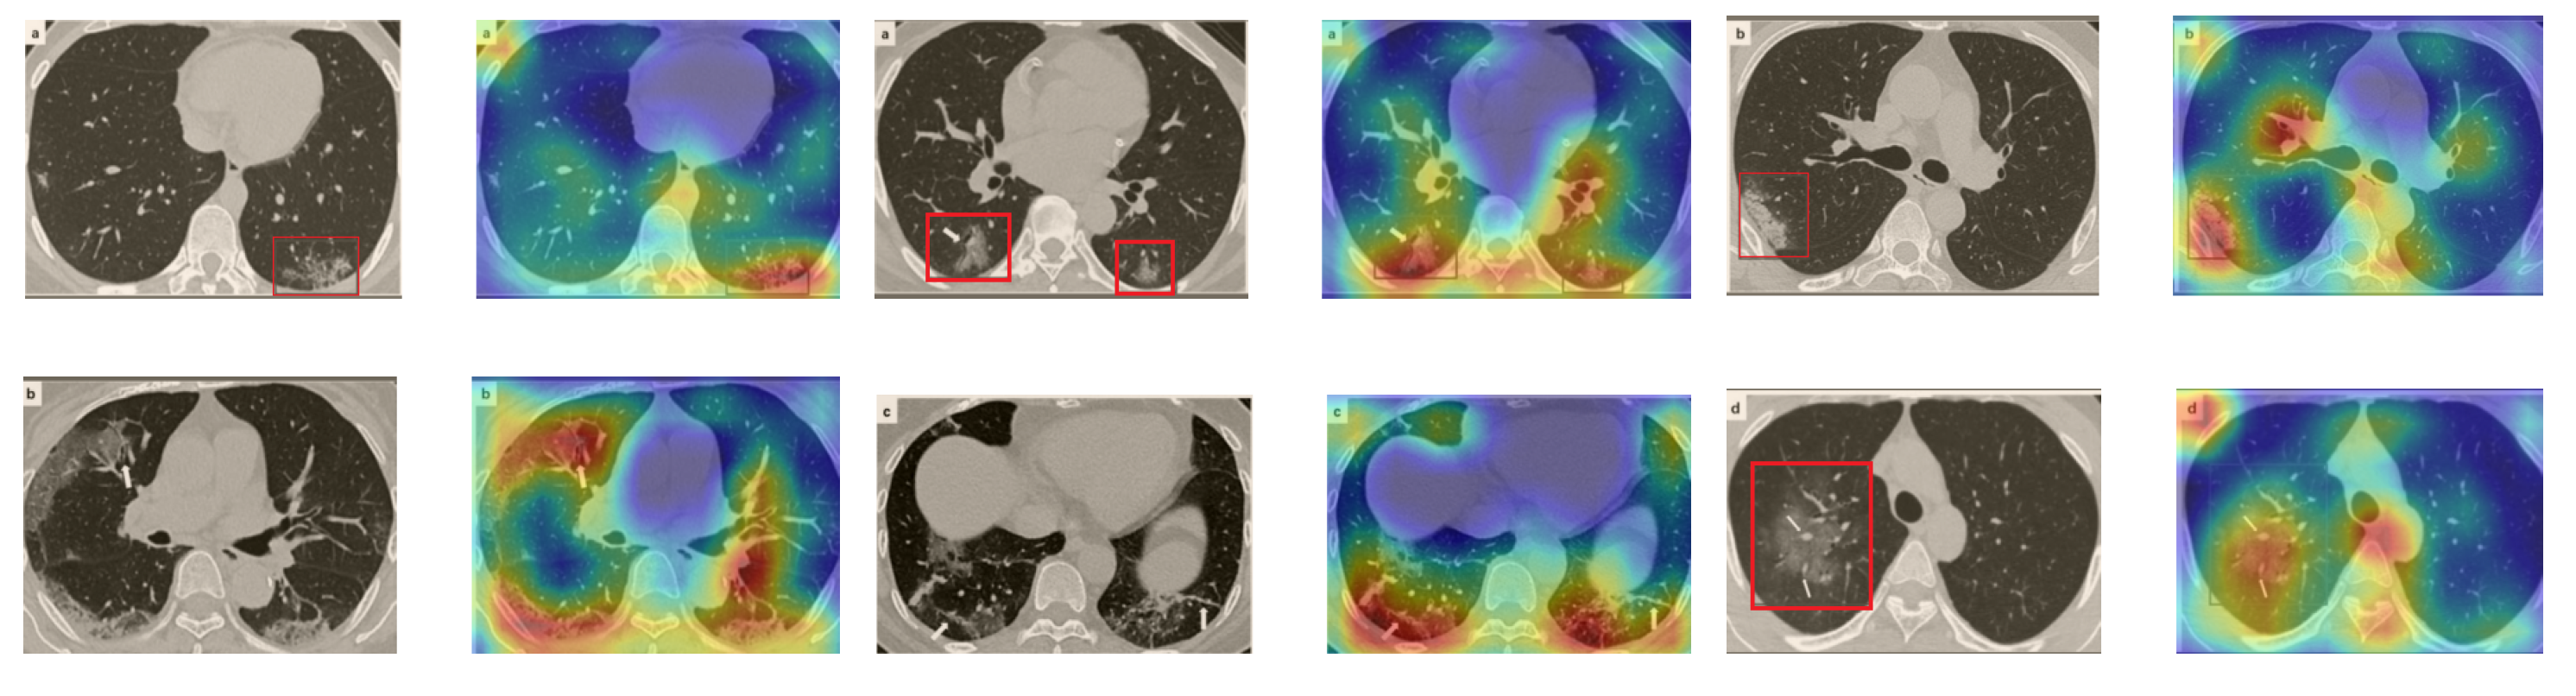

A wide variety of typical and atypical chest CT abnormalities of COVID-19 patients have been reported in various studies [61,62]. In order to investigate the ability of our models to identify COVID-19 cases outside the considered datasets and localize their CT findings, we tested our models on external CT images extracted from these two publications, as they feature typical findings of COVID-19 pneumonia marked by specialists. To make sure that none of the extracted images were unintentionally included in our datasets, specifically the COVID19-CT dataset, we used the model trained on the SARS-CoV-2 dataset. First, the InceptionV3 model was used to classify the extracted CT images. The model was able to correctly classify the given CT images as COVID-19. Second, in order to interpret the model’s generalization capabilities, we applied the Grad-CAM technique to visualize the regions of abnormalities that are considered. By assessing the different CT images in Figure 15, we can see that the model accurately localizes the disease-related regions. Even more interesting is the fact that the model ignores any specific marks in the images such as the letters and only localizes the COVID-19-related regions. These further experiments prove the success of our models to learn distinguishable visual features related to COVID-19, and to correctly classify CT images outside the datasets on which they are trained and tested.

Figure 15.

Examples of CT images taken from these two publications [61,62]. The CT images were correctly classified as COVID-19 cases, and the abnormal regions are accurately detected as in the localization maps.

In order to investigate the capacities of the different models to accurately localize identical or similar important regions, we employed the model with the lowest accuracy, i.e., SqueezeNet, which was fine-tuned on the SARS-COV-2 dataset to classify the unseen CT images taken from [61,62]. Moreover, we provide the Grad-CAM localization maps for a direct comparison. Figure 16 illustrates CT images, which represent the first two rows in Figure 15, and their corresponding localization maps. For most of the cases, both models looked exactly at similar regions representing the COVID-19 manifestations. However, for some images, SqueezeNet looked at irrelevant regions, such as the top left corner.

Figure 16.

Grad-CAM visualizations for the same CT images in the first two rows of Figure 15. The CT images were correctly identified by SqueezeNet as COVID-19 cases with relevant localization of the disease-related regions.